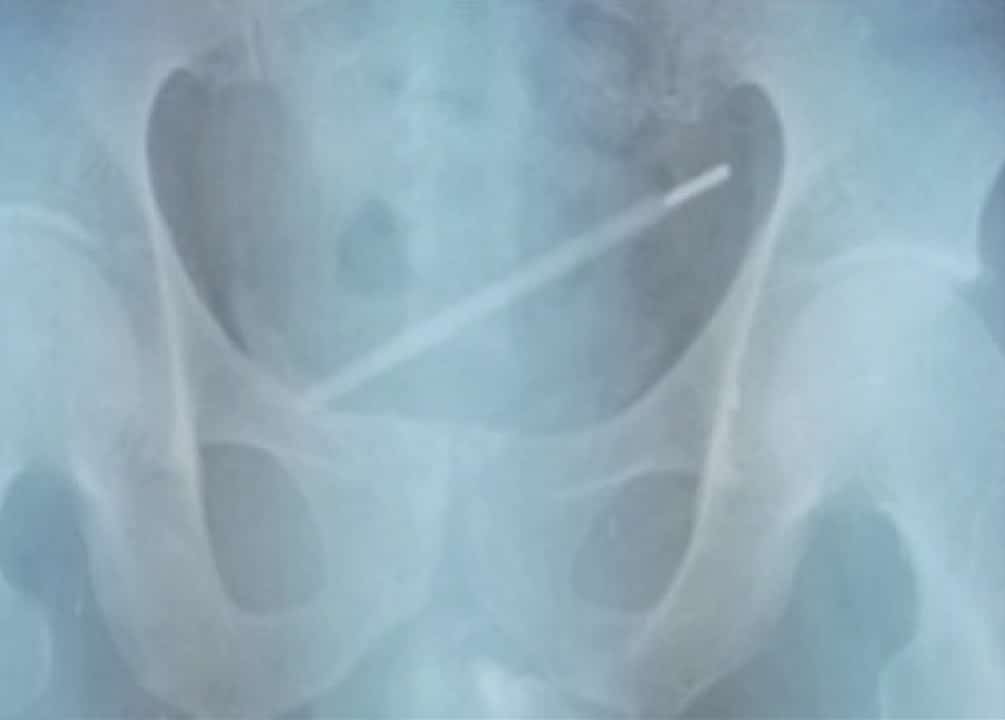

Un termometro di vetro all’interno del pene. È la singolare quanto pericolosa pratica sperimentata da un avventuriero del piacere fisico. Un giovane di Shanghai, 25 anni, è stato sottoposto alle cure mediche dopo aver introdotto nel suo organo sessuale lo strumento che misura la temperatura. A raccontarlo è il tabloid britannico The Sun, che cita una rivista scientifica, l’Urology Case Reports. Ad un certo punto il ragazzo ha perso il “controllo” e si è fatto strada all’interno del corpo, nella vescica.

Su Urology Case Reports, il dottor GanggangYang e i colleghi del Tongren Hospital hanno descritto il caso spiegando di averlo affrontato come si fa di solito per un calcolo renale. Il termometro è stata rimosso con l’assistenza di vari endoscopi, con estrattori di calcoli, evitando la chirurgia aperta come accade in molti altri casi. È stato utilizzato un lungo tubo sottile con una microcamera all’estremità. Con un paio di pinze i medici sono infine intervenuti per avere un’uscita più agevole dell’oggetto.

Sulla rivista medica di parla di “autoinserimento di un termometro per 11 giorni nell’uretra”, il canale che collega la vescica con l’esterno. I medici hanno spiegato che è stato eseguito un’azione “delicata per prevenire la rottura del termometro e per prevenire lesioni della parete vescicale. Ma non solo. Era necessaria l’attenzione massima perché il mercurio contenuto nel termometro è altamente tossico e può causare gravi danni ai reni e al sistema nervoso.